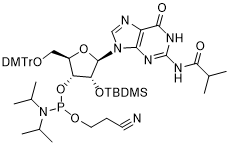

馬鞍山致研生物醫(yī)藥科技有限公司成立于馬鞍山市鄭浦港新區(qū)現(xiàn)代產(chǎn)業(yè)園。公司專(zhuān)注于生物小分子、醫(yī)藥中間體相關(guān)產(chǎn)品的研發(fā)和生產(chǎn),產(chǎn)品主要包括DNA亞磷酰胺單體、RNA亞磷酰胺單體、特殊單體以及按照客戶(hù)要求定制的RNA和DNA,并且公司提供定制合成等方面的研究服...

馬鞍山致研生物醫(yī)藥科技有限公司成立于馬鞍山市鄭浦港新區(qū)現(xiàn)代產(chǎn)業(yè)園。公司專(zhuān)注于生物小分子、醫(yī)藥中間體相關(guān)產(chǎn)品的研發(fā)和生產(chǎn),產(chǎn)品主要包括DNA亞磷酰胺單體、RNA亞磷酰胺單體、特殊單體以及按照客戶(hù)要求定制的RNA和DNA,并且公司提供定制合成等方面的研究服...